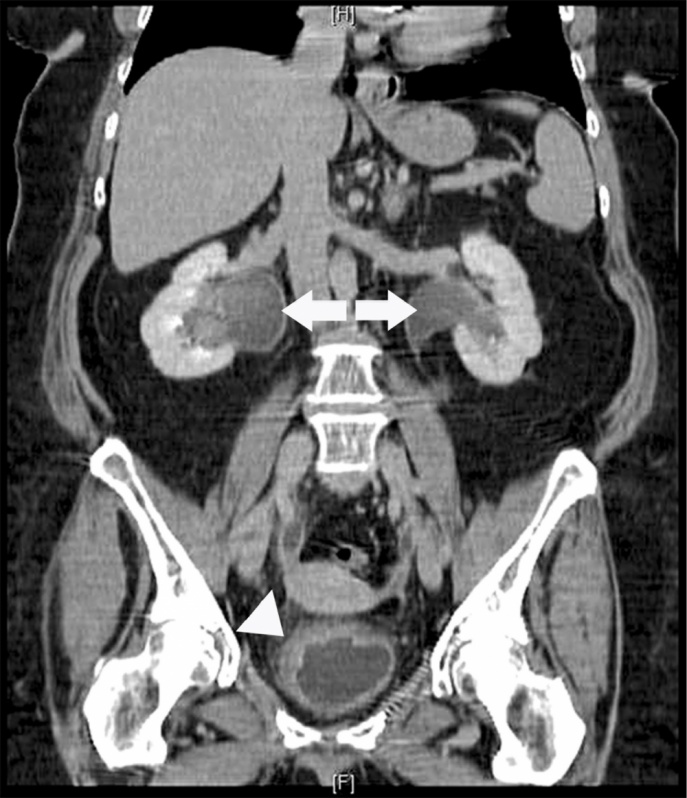

Exame de Imagem de Tomografia do Abdome Total

Medicom ExamesCom um exame de imagem é possível o médico analisar e ver o interior do corpo do paciente, para que desta maneira seja possível dar um diagnóstico para o paciente. O exame de imagem é diferente de...

Exame de Imagem de Tomografia do Abdome Total

Exame de Imagem de Tomografia do Abdome Total

Exame de Imagem de Tomografia do Abdome Total

Medicom ExamesCom um exame de imagem é possível o médico analisar e ver o interior do corpo do paciente, para que desta maneira seja possível dar um diagnóstico... Cotar Agora Saiba Mais